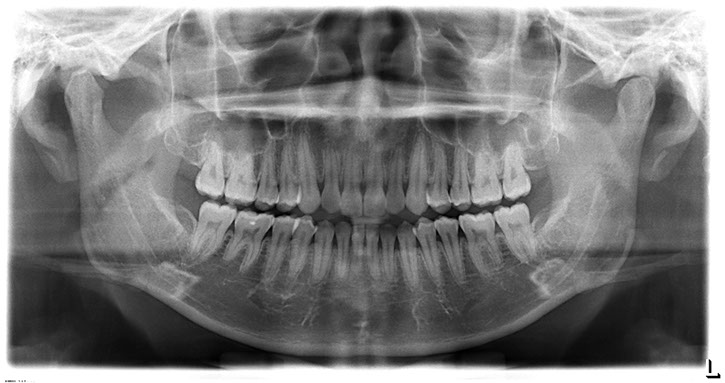

全口掃描X光攝影 (Panoramic x-ray)

全口掃描X光攝影(Panoramic x-ray)是一張環形掃描之全景X光攝影,它是齒顎矯正及植牙手術前一張不可或缺的影像,可以觀看到我們上下牙齒的形態、排列狀況,以及牙齦齒槽骨高度、與下頷神經管相關位置,亦可縱觀到顳顎關節(TMJ)、鼻竇(Sinus)、埋伏齒、囊腫(Cyst)或腫瘤(Mass)‧ ‧ ‧ ‧ ‧ ‧等等,同時可約略評估骨質狀態,因此它也常是醫療型全身健康檢查的例行項目之一。

一張好的全口掃描X光除了必須要有專業放射師的擺位、機器準確的定位外,影像清晰度的高低決定了它的診斷價值,我們提供高解析的數位化影像,亦可輸出雷射傳統X光片,讓您的牙醫師取得所需形式的報告來為您做最好的診斷。